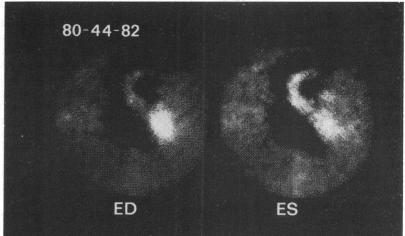

A method is described for measuring left ventricular ejection fraction which uses high frequency computer recording of gamma scintillation camera data and peripheral venous injectinon of technetium-99m as sodium pertechnetate. Data from mechanical model experiments are used to show feasibility of this method. A phantom experiment is described which was used to develop a technique for accurate delineation of the ventricular outline in the presence of background. The left ventricular ejection was measured in 12 patients by radionuclide angiocardiography and biplane cineangiography. Comparison of these two methods gave a correlation coefficient of 0-91. In addition, left ventricular ejection fraction was measured in 34 patients (aged 7 weeks to 18 years) without evidence of cardiac disease using the radionuclide method alone. Average ejection fractions of 0-66 and 0-70 were found for children over 2 years of age and children 2 years of age or younger, respectively. In addition, an interobseerver comparison study was performed with the data from 10 patients, and only small differences were noted (SD 0-025).

本文描述了一种测量左心室射血分数的方法,该方法利用γ闪烁照相机数据的高频计算机记录以及静脉注射高锝酸钠形式的锝-99m。机械模型实验的数据用于证明该方法的可行性。文中描述了一个体模实验,该实验用于开发一种在存在背景的情况下准确描绘心室轮廓的技术。通过放射性核素心血管造影术和双平面电影血管造影术对12例患者进行了左心室射血测量。这两种方法的比较得出相关系数为0.91。此外,仅使用放射性核素方法对34例(年龄从7周至18岁)无心脏病证据的患者进行了左心室射血分数测量。发现2岁以上儿童和2岁及以下儿童的平均射血分数分别为0.66和0.70。此外,对10例患者的数据进行了观察者间比较研究,仅发现微小差异(标准差0.025)。